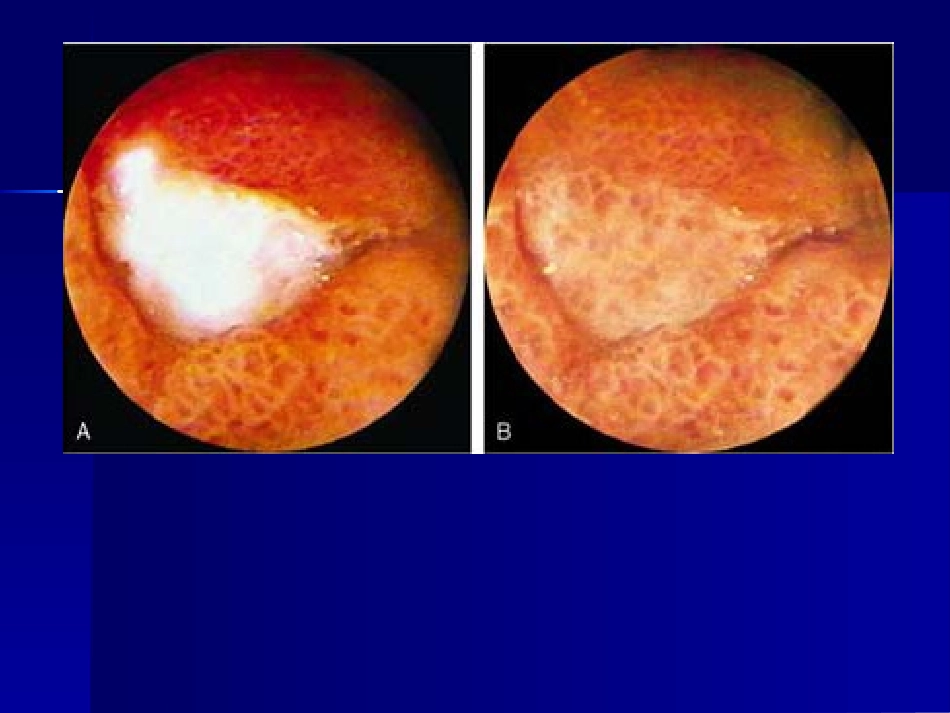

流行病学流行病学发病呈下降趋势发病呈下降趋势世界性分布.临床上GU多于DU,两世界性分布.临床上GU多于DU,两者之比者之比2-2-3:1.DU好发于青壮3:1.DU好发于青壮年,GU发病年龄较迟,平均晚十年。年,GU发病年龄较迟,平均晚十年。消化性溃疡的发作有季节性,秋冬和冬消化性溃疡的发作有季节性,秋冬和冬春之交比夏季常见。春之交比夏季常见。病因和发病机制病因和发病机制平衡学说平衡学说攻击因子攻击因子——胃酸、胃蛋白酶、微生物、胃酸、胃蛋白酶、微生物、胆盐、乙醇、药物、其他有害物胆盐、乙醇、药物、其他有害物防御修复因子防御修复因子——粘液/碳酸氢盐屏障、粘液/碳酸氢盐屏障、粘液屏障、粘液血流量、细胞更新、前列腺粘液屏障、粘液血流量、细胞更新、前...